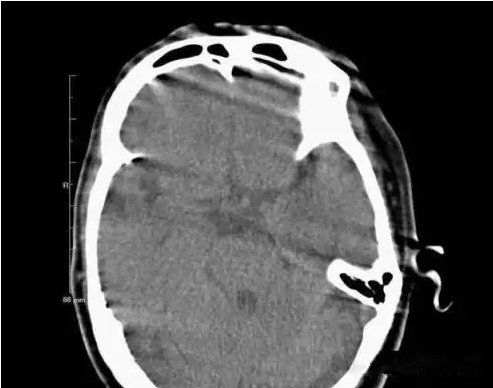

1、運動偽影

在掃描過程中,如果病人體位發(fā)生變化,可造成圖像數(shù)據(jù)排列紊亂。重建圖像結(jié)構(gòu)模糊,無法分辨。運動偽影又分為自主運動偽影和生理性運動偽影。

(1)自主運動是指那些患者可以控制的運動,如呼吸運動、體位移動等。

(2)生理性運動是隨機的,不能由患者自主控制,如心臟管搏動、胃腸蠕動等。

(運動偽影)